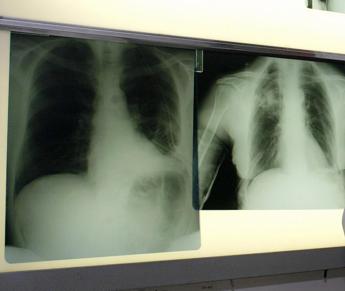

Nuova terapia per il cancro al polmone con mutazione Egfr in stadio precoce ha raggiunto una sopravvivenza senza precedenti nella malattia con l’88% dei pazienti vivo a cinque anni. I risultati positivi dello studio di fase III Adaura hanno mostrato che osimertinib, questo il nome del farmaco sviluppato da AstraZeneca, ha prodotto un miglioramento statisticamente significativo e clinicamente rilevante della sopravvivenza globale rispetto a placebo, nel trattamento adiuvante del carcinoma polmonare non a piccole cellule (Nsclc) in stadio precoce (IB, II e III A) che presenta mutazioni del recettore del fattore di crescita epidermico (Egfr), a seguito di resezione radicale. Sono questi i risultati illustrati oggi al Congresso annuale 2023 della Società americana di oncologia clinica (Asco) e pubblicati contemporaneamente sulla rivista The New England Journal of Medicine.

Osimertinib – si legge in una nota – ha ridotto il rischio di morte del 51% rispetto a placebo, sia nella popolazione dell’analisi primaria (stadio II-IIIA) che nella popolazione complessiva dello studio (Stadio IB-IIIA). Nella popolazione dell’analisi primaria, l'85% dei pazienti trattati con osimertinib è vivo a cinque anni rispetto al 73% dei pazienti trattati con placebo. Nella popolazione complessiva dello studio, l'88% dei pazienti trattati con osimertinib è vivo a cinque anni, rispetto al 78% di quelli trattati con placebo. La sopravvivenza globale mediana non è stata raggiunta sia nel braccio sperimentale che nel gruppo di controllo. I pazienti trattati con placebo che hanno sviluppato malattia metastatica hanno avuto l’opportunità di ricevere osimertinib come trattamento successivo. “Negli stadi precoci di malattia l’intento del trattamento è curativo – spiega Filippo de Marinis, direttore della Divisione di Oncologia Toracica dell’Istituto Europeo di Oncologia di Milano e Principal Investigator dello studio Adaura per l’Italia – La tradizionale chemioterapia non riesce a impattare in maniera significativa sulla diminuzione del rischio di recidiva di malattia locale o a distanza in percentuali superiori al 5%. Questi nuovi risultati dello studio Adaura dimostrano che quasi il 90% dei pazienti con tumore del polmone non a piccole cellule in stadio iniziale trattati con Osimertinib è vivo a 5 anni, con una riduzione del rischio di morte del 51%. La rilevanza di questi dati è senza precedenti: osimertinib è il primo inibitore tirosino-chinasico dell’Egfr a dimostrare un beneficio in sopravvivenza complessiva nel setting adiuvante nei pazienti con carcinoma polmonare non a piccole cellule Egfr mutato e sottoposti a chirurgia radicale. Risultati ancora più importanti se consideriamo che, nella malattia operabile, la sopravvivenza a 5 anni diminuisce dal 73% nello stadio IB fino al 41% nel IIIA. Il beneficio di osimertinib si estende a tutti i sottogruppi di pazienti. Infatti, negli stadi II-IIIA la sopravvivenza a 5 anni ha raggiunto l’85%. I risultati di Adaura rinforzano ulteriormente il beneficio di osimertinib quale standard di cura dopo la chirurgia nei pazienti con malattia in stadio precoce e positivi alla mutazione di Egfr”. “Nel 2022, in Italia, sono stati stimati quasi 44mila nuovi casi di carcinoma polmonare – afferma Saverio Cinieri, presidente Associazione italiana di oncologia medica (Aiom) -. Circa il 30% dei pazienti colpiti dalla forma non a piccole cellule riceve una diagnosi di malattia abbastanza precocemente da poter essere sottoposto a intervento chirurgico con intento radicale. Ciononostante, la recidiva è ancora frequente nel tumore agli stadi iniziali. Per questa ragione accogliamo positivamente i risultati dello studio Adaura, a conferma ulteriore dei grandi progressi che sta compiendo la ricerca in oncologia. È importante il ruolo rivestito da terapie mirate ed efficaci come osimertinib che portano di fatto a un miglioramento del percorso terapeutico del paziente e aumentano le possibilità di sopravvivenza a lungo termine”. “La chirurgia rimuove il carcinoma e taglia al livello macroscopico, ma non riesce a incidere su quello microscopico – sottolinea de Marinis -. Resta, cioè, un ‘microscopico invisibile’ rappresentato dalle micrometastasi, che si muovono nel sangue e nella linfa e incidono sulla ricaduta locale o a distanza della malattia nel tempo. Circa la metà dei pazienti con tumore di stadio I-II e tre quarti dei pazienti di stadio III presentano una recidiva a cinque anni dall’intervento. La disponibilità di osimertinib rende necessario eseguire, in tutti i pazienti operati, l’esame molecolare per verificare l’alterazione del gene Egfr, perché così possiamo individuare i pazienti candidabili alla terapia mirata”. Alla precedente analisi della sopravvivenza libera da malattia – prosegue la nota – tutti i pazienti avevano completato o interrotto il trattamento. La sicurezza e tollerabilità di osimertinib al follow-up esteso è risultata in linea con il profilo consolidato e con le analisi precedenti, senza nuove segnalazioni di sicurezza. Gli eventi avversi di Grado ≥3 per tutte le cause si sono verificati nel 23% dei pazienti nel braccio con osimertinib rispetto al 14% in quello con placebo. Il tumore del polmone è la causa principale di morte per cancro tra gli uomini e le donne, e rappresenta circa un quinto di tutti i decessi per cancro. Il tumore del polmone si suddivide in Nsclc e tumore del polmone a piccole cellule. Si stima che ogni anno, a livello globale – conclude la nota – 2,2 milioni di persone ricevano una diagnosi di tumore al polmone, di cui l’80-85% classificato come Nsclc, la tipologia più comune. La maggior parte dei pazienti con Nsclc presenta una diagnosi di malattia avanzata, mentre circa il 25-30% presenta malattia resecabile alla diagnosi. Le diagnosi di cancro al polmone in fase iniziale vengono spesso rilevate solo quando il cancro viene identificato mediante indagini radiologiche effettuate per altre condizioni non correlate. La maggior parte dei pazienti con tumore resecabile sviluppa una recidiva nonostante la resezione completa del tumore e la chemioterapia adiuvante. Inoltre, solo il 73% dei pazienti in Stadio IB e il 56-65% di quelli in Stadio II sopravvive a cinque anni. La percentuale scende al 41% nei pazienti in Stadio IIIA, il che dimostra una elevata necessità medica insoddisfatta. —salutewebinfo@adnkronos.com (Web Info)